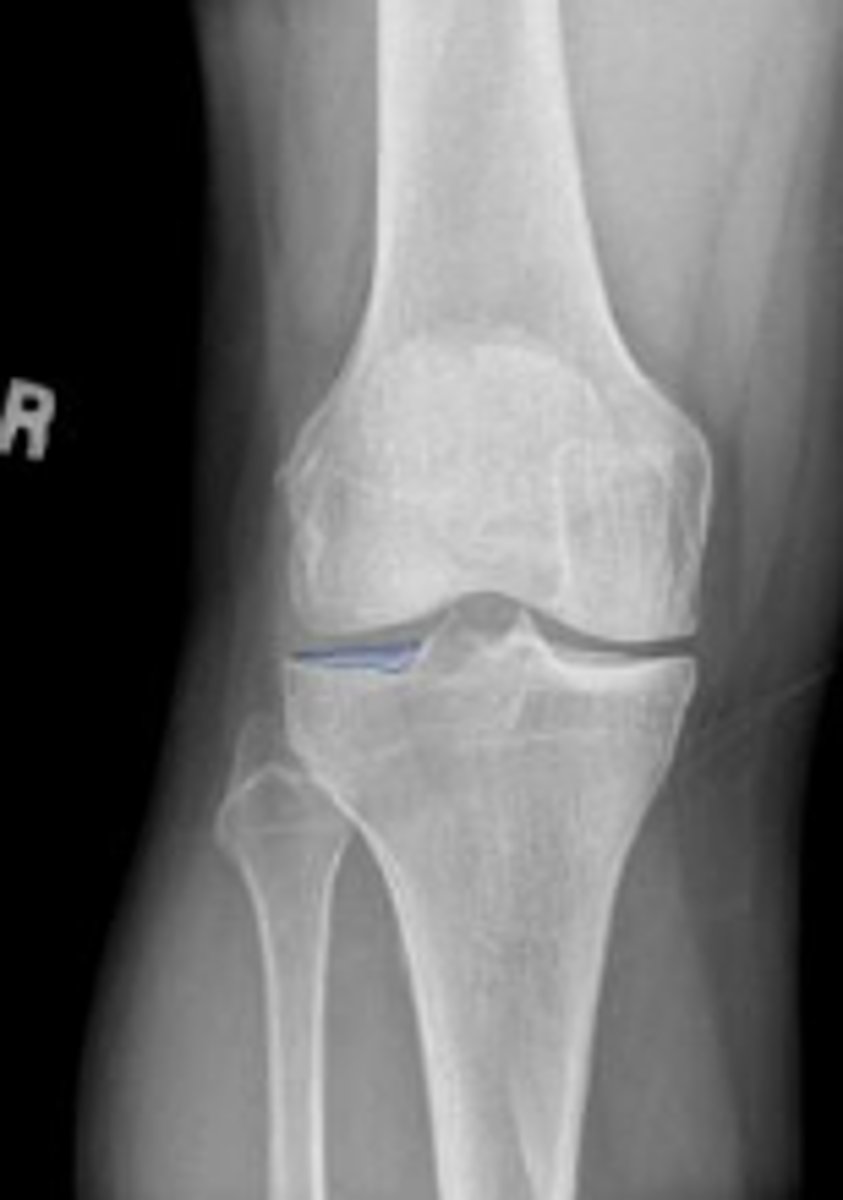

Right internal oblique knee

What is the name of the radiographic view?